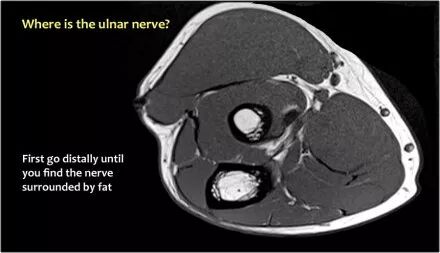

因此,当我们回到图像时,您会发现很难找到神经。任何这些皮下结构都可以是转位神经。一种方法是远端跟随结构,直到你发现远端的尺神经位于由脂肪包围的前臂近端的正常位置。然后当你向近端跟随它时,你会发现这是皮下移位。